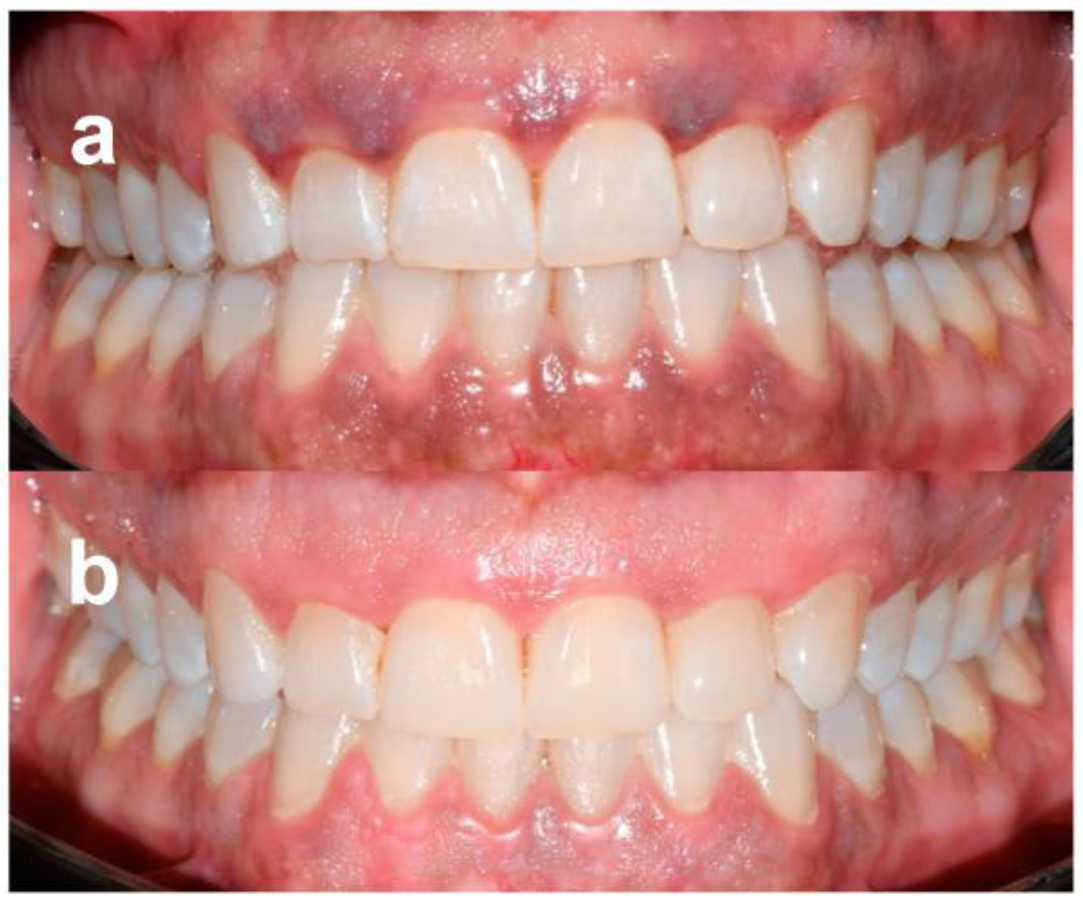

Patients were followed-up regularly, and no recurrences were observed over a minimum follow-up of 12 months (Figure 2 and Figure 3). At the same time point, all patients were available to repeat the treatment if necessary (YES) (Table 4).

Figure 2. Patient no. 1: Preoperative clinical aspect (a) and follow-up 1 year after laser application (one session) (b).

Figure 3. Patient no. 6: Preoperative clinical aspect (a) and follow-up 1 year after laser application (two sessions) (b).